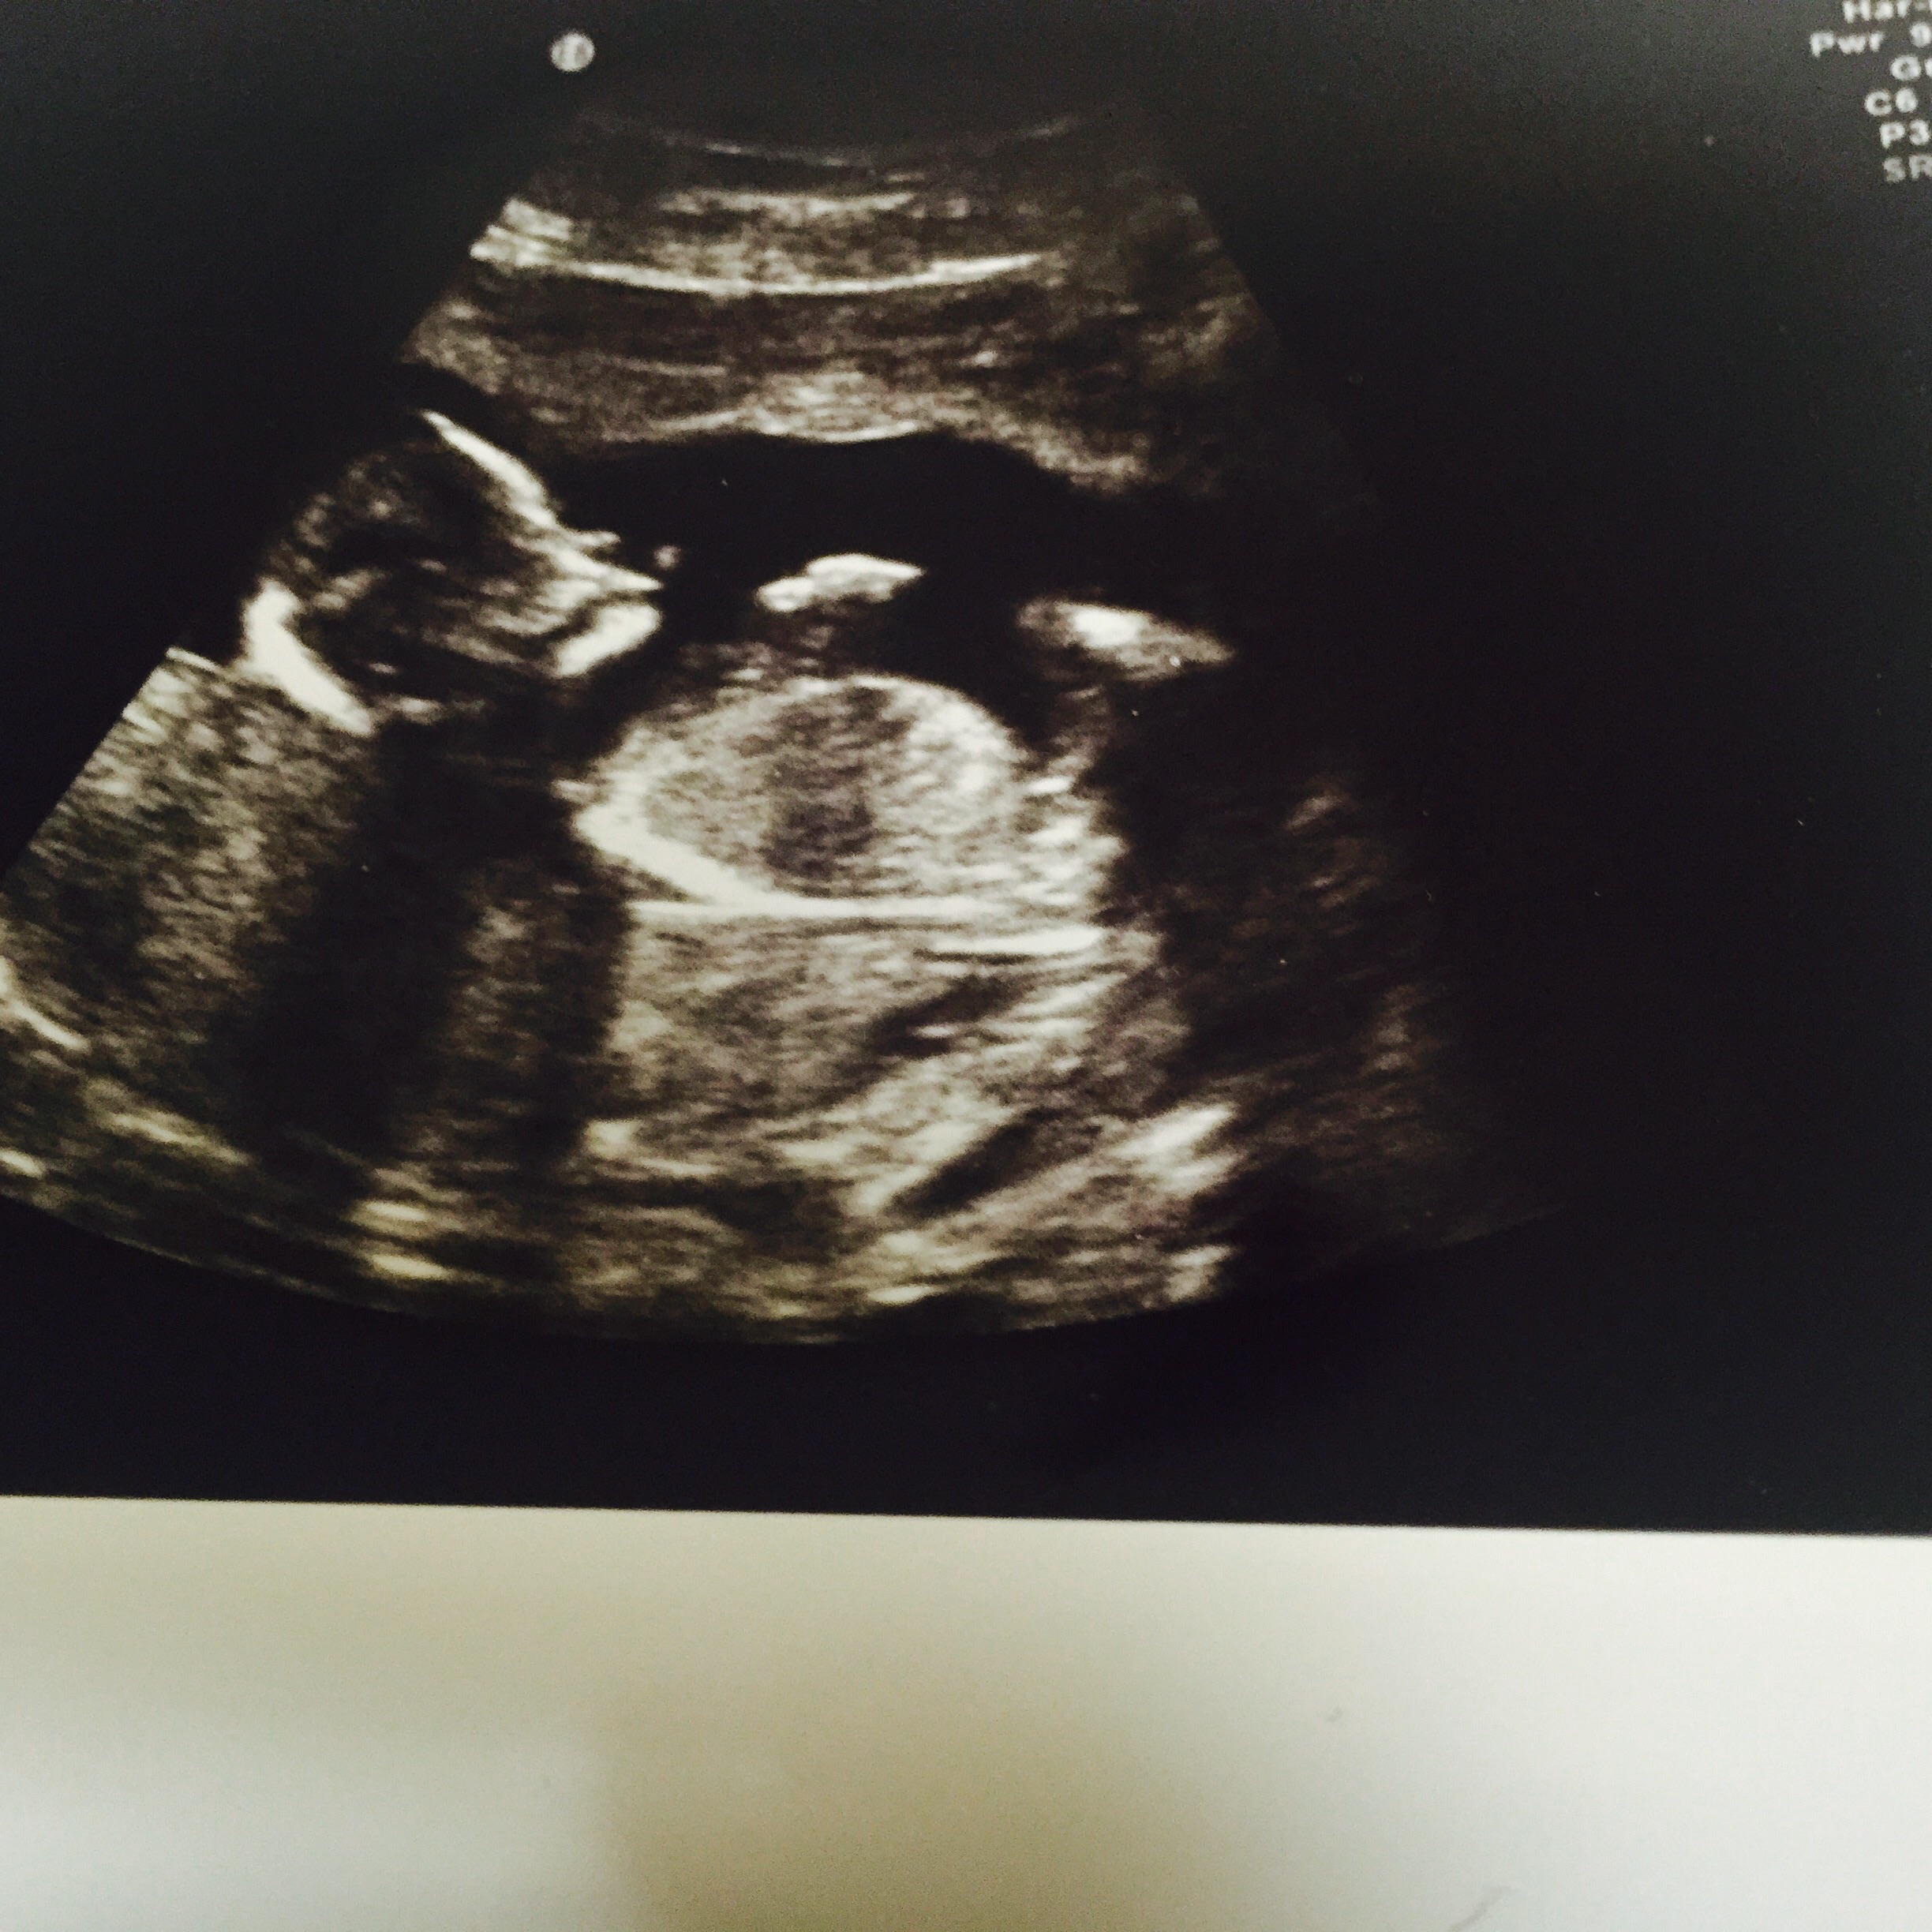

Unusual nub please please help!?! :)

I have what seems like a very unusual nub on this scan pic and none of the other sites seems to be able to guess - please can you try

It's definately not the textbook boy nub in fact I can't say I've seen one looking like this in any of the millions of pics I have seen online either

Desperately need support also if you can tell me how you interpreted it I would be so grateful

This was taken at 14+5 thanks so much xxx